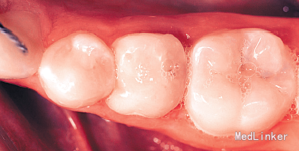

左下第二乳磨牙滞留,上下牙列轻度拥挤不齐.全景示左下第二乳磨牙无相应的恒牙,先天缺失35牙

诊断:35牙缺失,牙列不齐 治疗:排齐整平上下牙列,对滞留的乳磨牙处理如下:因乳磨牙宽大,较正常前磨牙近远中径大很多,正畸治疗过程中逐次给乳磨牙减径后树脂修复参与正畸治疗,使减径树脂修复后的乳磨牙宽度为以后修复的前磨牙宽度一致。减径后的间隙留作牙列内其他牙齿的排齐。